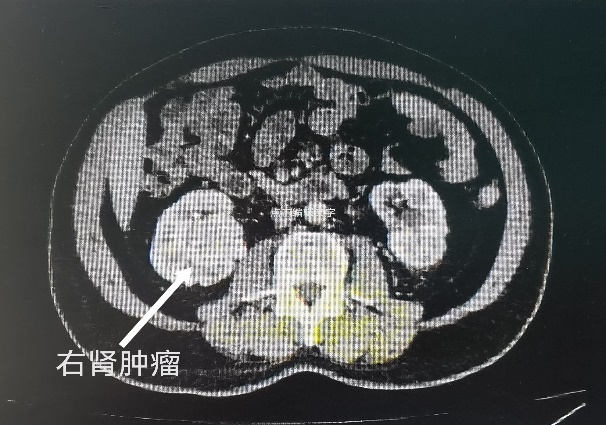

入院后,经过全方面检查与多次会诊,在同患者进行深入沟通后,张奇夫教授决定为李大爷进行保留肾脏的手术。张奇夫教授表示,临床上对于肾癌常用的手术方式有两种:一种是单纯切除肿瘤,保留正常肾组织;另一种是根治性肾切除手术,将整个肾和肿瘤一起切除。李大爷患有双侧肾癌,如果根治性双肾切除,对于医生来讲,手术就没有什么特殊难度了,但是对于李大爷来讲,终生的透析不仅是经济负担,更是严重影响生活质量。他的双肾肿瘤体积均超过了4厘米,并且右肾肿瘤属于肾内型,长在肾脏的中央,肿瘤紧邻肾脏集合系统与肾脏血管,手术风险和难度太大,患者左肾既往做过结石手术,肾脏周围瘢痕黏连较重,左肾形态已经有所改变,手术也存在不确定性。但考虑到患者强烈的保留肾脏意愿,行“肾部分切除术”是最佳选择。同时,他判断,该患者双侧肾脏不宜同时手术,那样对肾脏打击太大,容易出现肾功能衰竭。综合病情,左侧肾脏切除肿瘤保留肾脏的成功率较大,因此决定先行左侧肾脏的保肾手术。

经过充分的术前准备,2022年10月,张奇夫教授团队为李大爷进行了左肾部分切除术。术中情况正如术前预料的一样,因患者左肾既往做过结石手术,肾脏周围黏连明显,手术难度较大。但在团队的通力配合下,还是顺利完成了手术。术后的病理检查结果是透明细胞癌,也证实了术前的诊断。术后经过精心的护理和治疗,李大爷恢复的很好,顺利出院修养,为第二次右肾的手术做好准备,医生们对于接下来的治疗也充满了信心。

2023年1月,李大爷返回色情导航 准备第二次手术。然而术前的检查结果并不是非常理想,虽然右肾的肿瘤体积没有明显增大,抽血化验肾功能也没发现明显异常,但是通过肾动态显像检查发现,李大爷的两侧肾脏功能都不理想。左肾因为经过结石和肿瘤两次手术,左肾功能还不到正常的二分之一,右侧肾脏因为肿瘤的影响,功能也处于较低水平。如果接下来的手术没有保留住右侧肾脏将右侧肾脏切除,术后极大可能会出现肾功能衰竭,需要透析治疗。面对这种情况,医生们也感到了很大压力,经过全面的术前检查与病情评估,考虑到术中各种情况与细节,并经过麻醉科会诊,张奇夫教授带领团队医生下定决心,一定要保住李大爷的右肾。